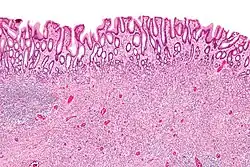

| Low magnification micrograph of an inflammatory fibroid polyp. H&E stain. | |

An inflammatory fibroid polyp presents histologically as an exuberant,[10] non-encapsulated, localized proliferation of spindle-shaped mononuclear cells,[4] with an inflammatory infiltrate that is frequently dominated by eosinophils.[33] The fuzzy borders visible on endoscopic ultrasound correspond with the non-encapsulated proliferating spindle cells.[34] Most inflammatory fibroid polyps are vascular, consisting of a network of varying diameter blood vessels.[35] Occasionally, the spindle-shaped cells are arranged in a concentric pattern that resembles "onion skin".[36][4] Surface ulceration in focal areas can occasionally be observed.[6] Though usually polypoidal,[7] the lesion is thought to originate in the lower layer of the lamina propria[23] and may be sessile.[24][7] The layers of the muscle wall atrophy, fraying, and splitting are brought on by inflammatory fibroid polyps.[6]